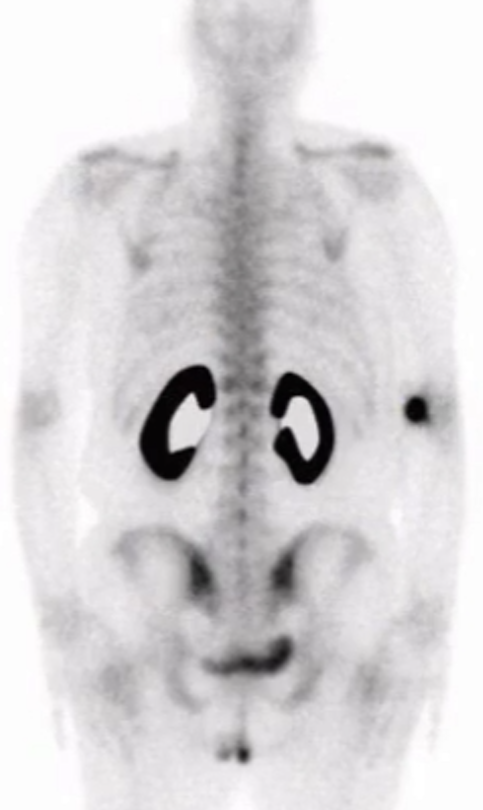

PSMA

• Will see salivary glands are dark if PSMA is used

• If have contamination of this process with water or air (pull back on syringe) or not enough stannous ions (tin) you will have more free Tc than can bind and you will have uptake in the study in the salivary glands

• Air contamination = free Tc = hot salivary glands, gastric tissue, thyroid

• Not enough stannous ions = same as air contamination = free Tc

Free Tc

• Hardly see bones (no bone uptake)

• Uptake in stomach

• Uptake in salivary glands

• Uptake in thyroid